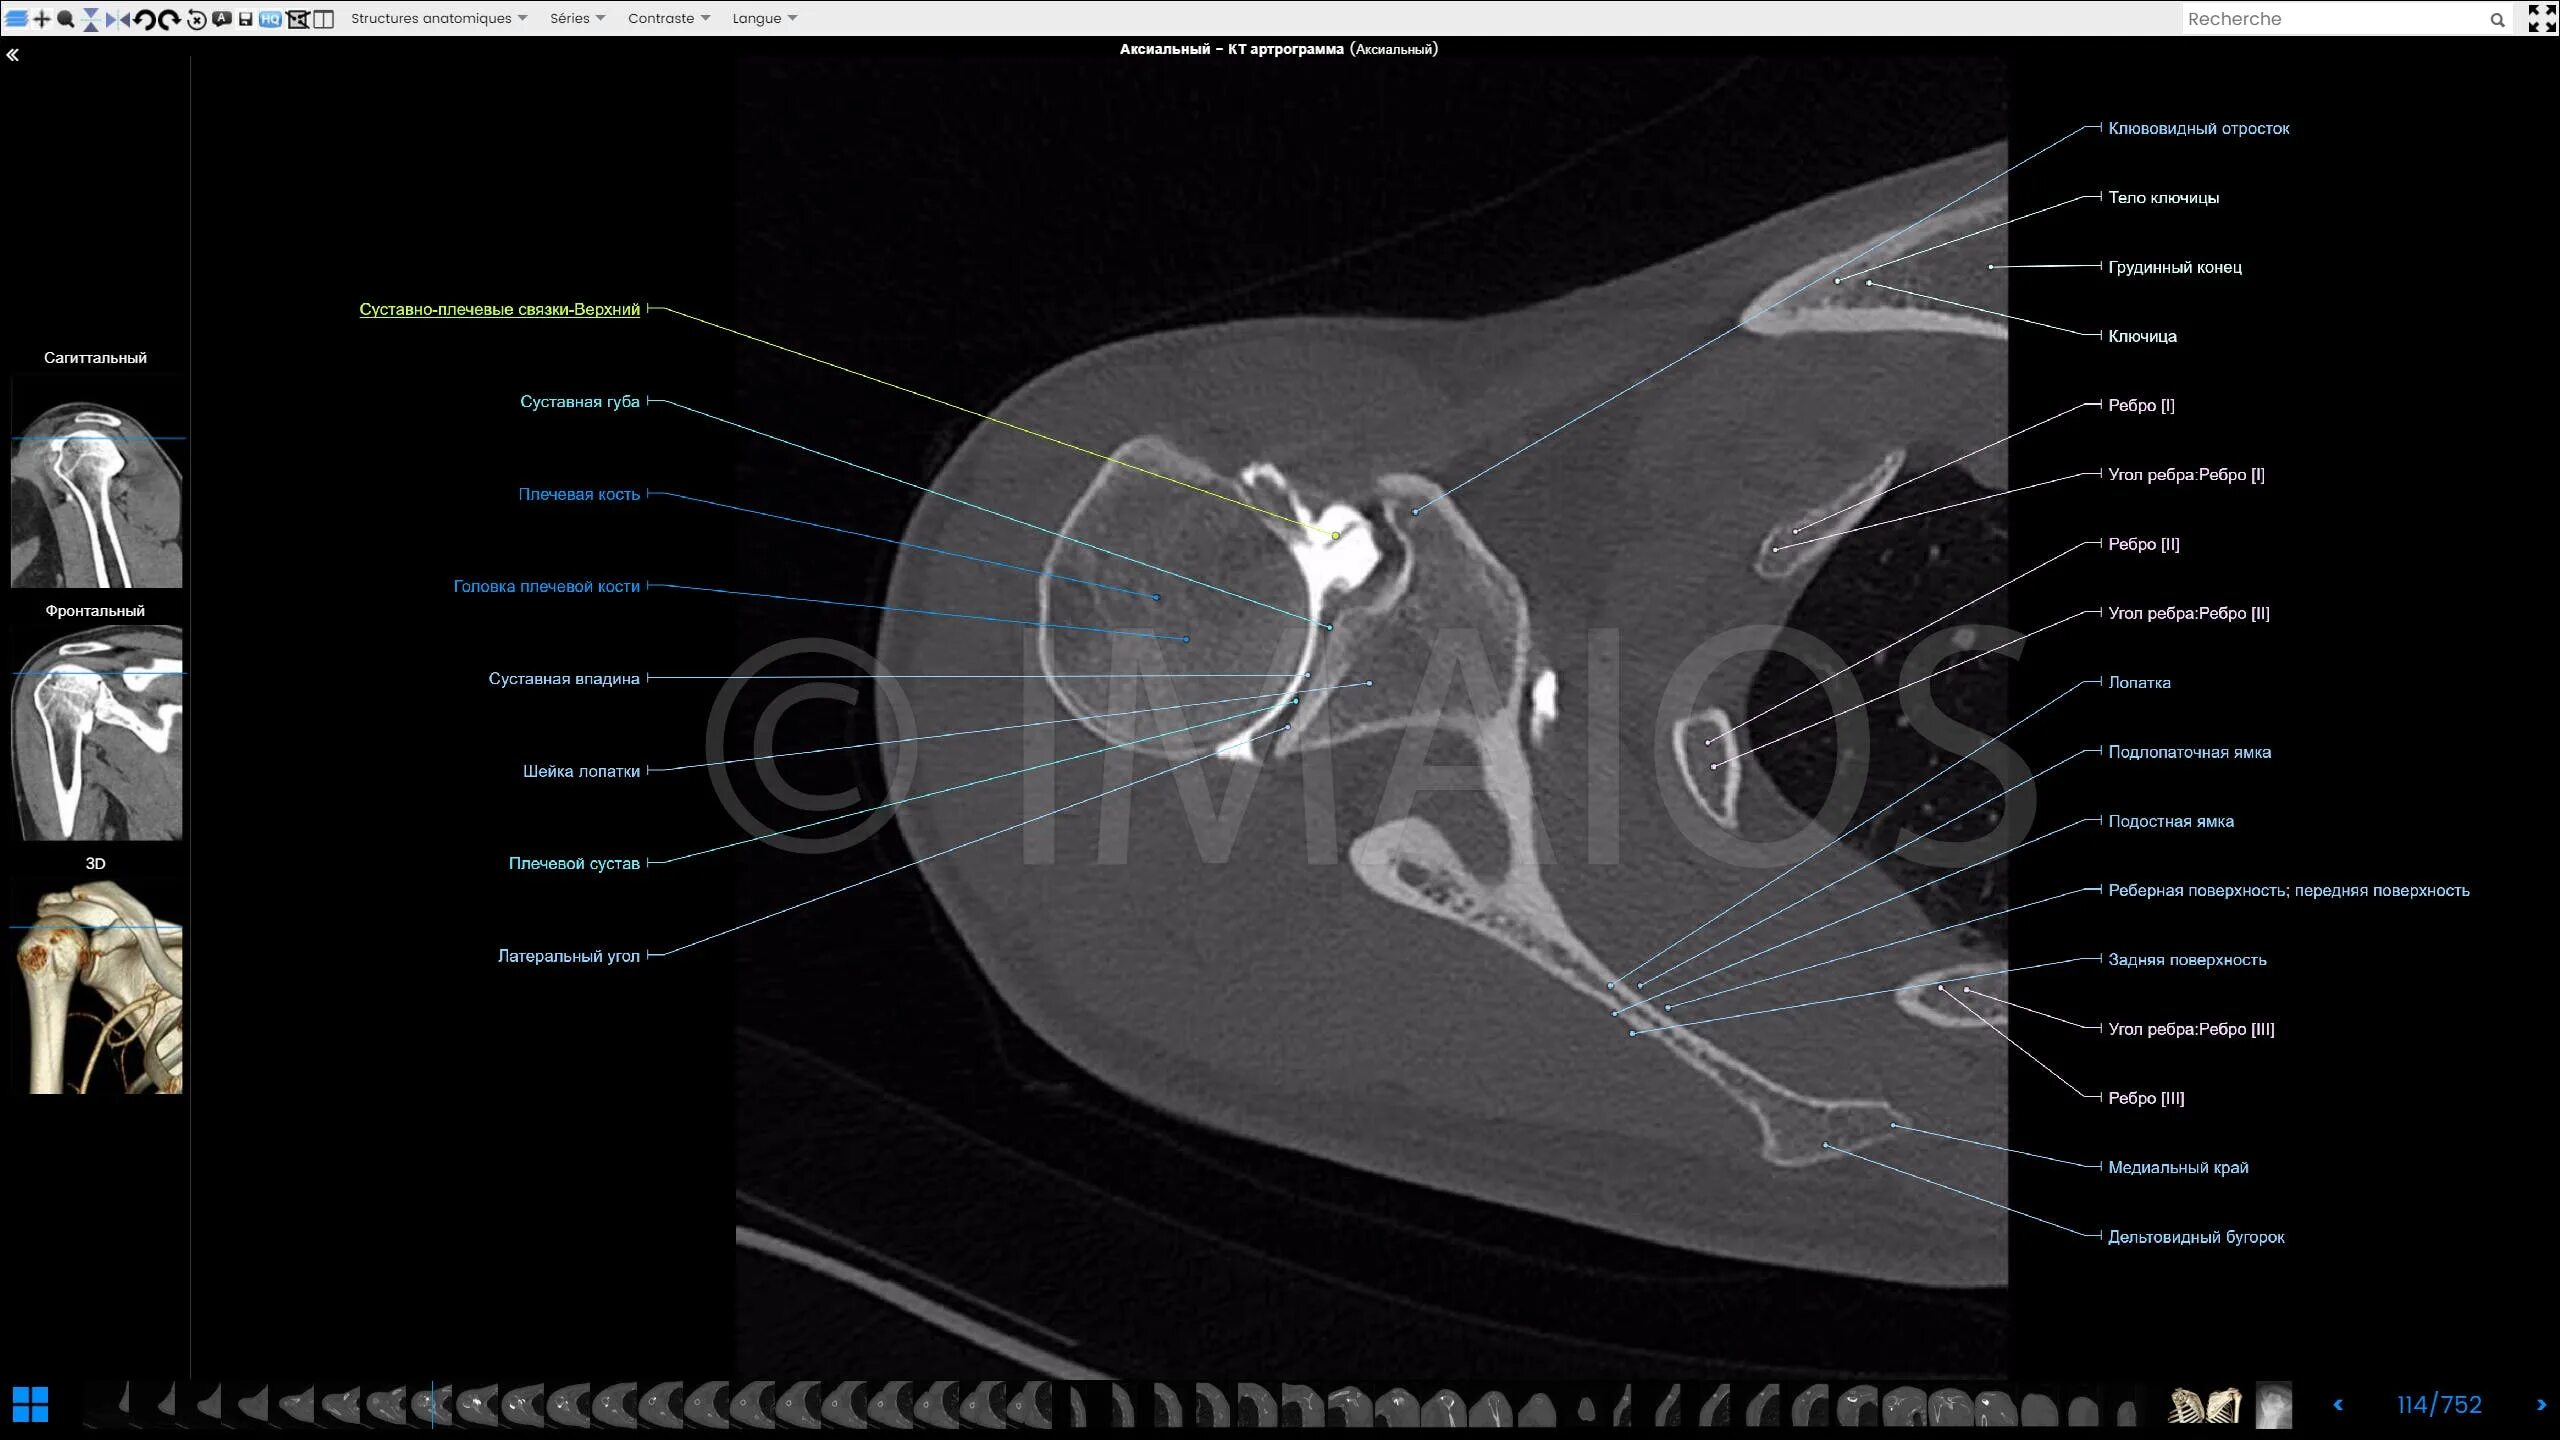

Ошибки кт